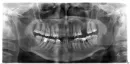

1. Зуб "восьмерка" нижняя слева. При нажатии на десну около него выходит гной (достаточно много). Один врач сказал полоскать содой с йодом. Делала - не помогло. Другой сказал промывать из шприца хлоргексидином и перекисью, потом закладывать "дента...." (не совсем помню). Проделала и это - не помогло. Потом сказали, что нужно надрезать десну и как следует оголить коронку. Надрезали - и опять ничего. Гной продолжает вытекать при надавливании.

2. Зуб "шестерка" нижняя слева. Этот зуб у меня на штифтах, достаточно давно. Если провести пальцем у его основания – чувствуется ужасный запах.

3. Зуб "пятерка" верхняя слева. Насколько смогла ее рассмотреть через зеркало - не нравится, как будто "черная дырка", с внутренней стороны. Одни врачи говорят под удаление, другие под коронку.

4. Отсутствует "шестерка" верхняя слева. Здесь стоит вопрос - имплант или мостик? Наверное, это тоже как то зависит от того, что делать со всем тем, что я спросила в предыдущих вопросах.

Все эти три зуба необходимо удалить, неужели ваши стоматологи не видят по снимкам, что все эти зубы разрушены и сгнили. На четвёртый вопрос я думаю, ответ очевиден.